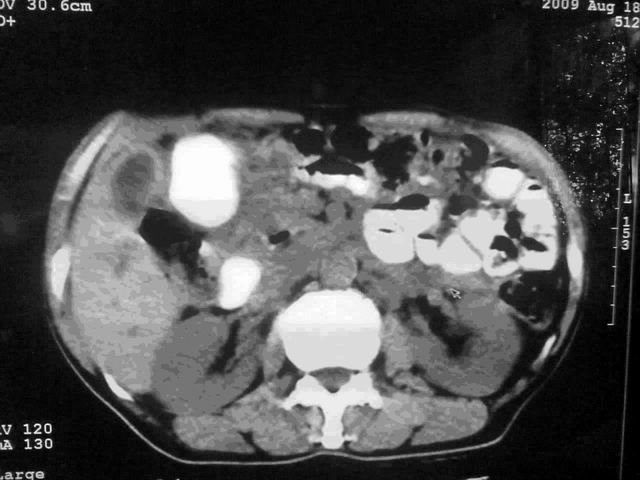

我这个考考大家眼力,看看是升结肠ca还是降结肠ca

伪影太多,考虑降结肠癌伴肝转移,胆囊炎

伪影太多,考虑升结肠癌伴肝转移,胆囊炎

片子质量差了点,好像是降结肠

考虑升结肠癌伴肝转移;胆囊炎。

明确考眼力!考虑降结肠癌伴肝转移可能性。

考虑升结肠癌伴肝转移;胆囊炎

伪影太多,考虑降结肠癌伴肝转移,胆囊炎。